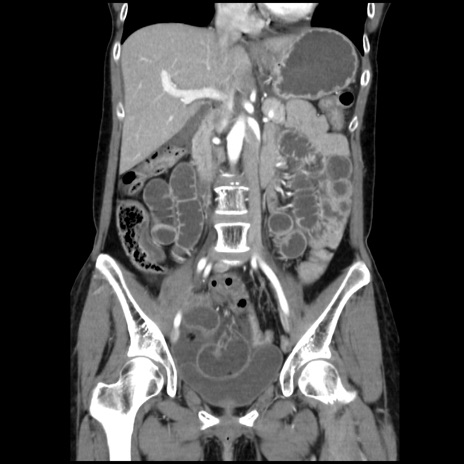

症例32(冠状断像)

【症例】40歳代 女性

【主訴】上腹部痛、嘔気・嘔吐

【現病歴】約9時間前頃から急に上腹部痛、嘔気、嘔吐が出現。改善しないため救急要請。

【既往歴】子宮頚癌(広汎子宮全摘術、放射線療法)、腸閉塞

【身体所見】腹部:平坦、軟、腸雑音亢進、上腹部を中心に腹部全体に圧痛あり。

【データ】WBC 8400、CRP 0.03